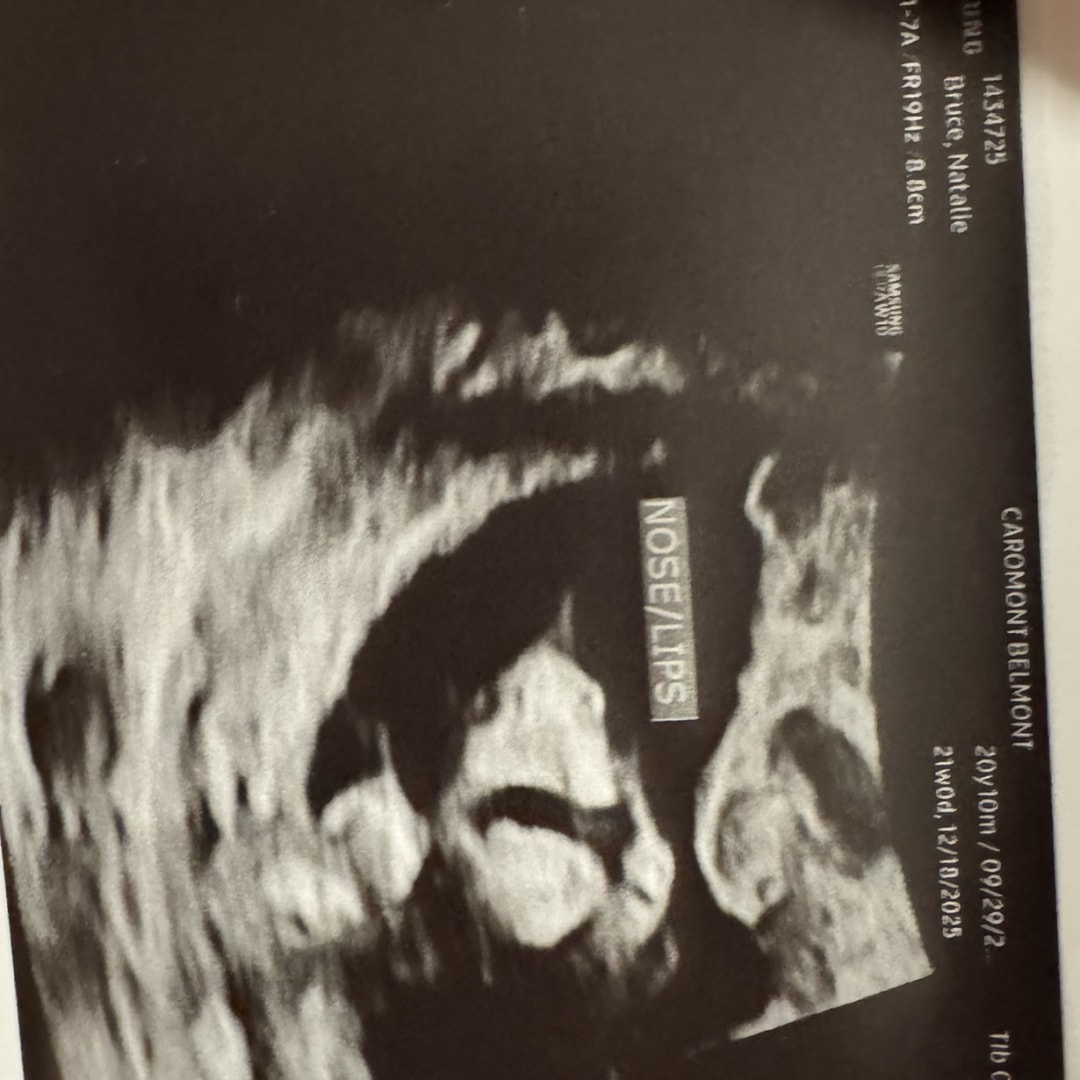

20 weeks